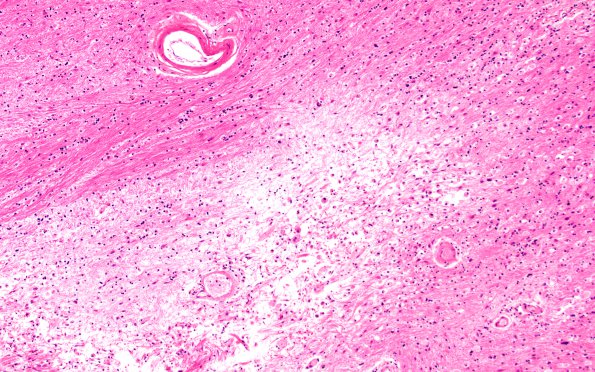

Subcortical Arteriosclerotic Encephalopathy

6B2 (Case 6) H&E 10X 1

Higher magnification image of #6B2. (H&E)